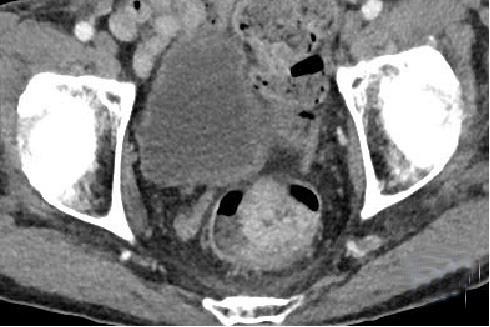

• 计算机体层摄影血管造影在腹腔镜结肠癌根治术前评估中的应用效果

2025, 31(6):24-31. DOI: 10.12235/E20240177

摘要 (181) HTML (147) PDF 4.65 M (171) 评论 (0) 收藏

摘要:目的 分析计算机体层摄影血管造影(CTA)在腹腔镜结肠癌根治术前评估中的应用效果。方法 回顾性分析2021年1月-2024年2月于该院接受腹腔镜结肠癌根治术的120例患者的临床资料。其中,60例行常规腹部CT和CTA,60例行磁共振成像(MRI)。以术后病理为金标准,判断CTA对临床T分期与术后病理的一致性,以及评估肿瘤是否侵犯肠系膜血管和周围组织的准确度。结果 术前CTA诊断T分期的准确率为95.00%(57/60),一致性好(Kappa = 0.925,P < 0.05);术前MRI诊断结肠癌T分期的准确率为98.33%(59/60),两者比较,差异无统计学意义(χ2 = 0.26,P > 0.05)。CTA预判肿瘤是否累及肠系膜上动脉、肠系膜上静脉、肠系膜下动脉、肠系膜下静脉、腹主动脉、肾动脉、肾静脉和脾动脉等血管,与术后病理的一致性好。特别是在预测肠系膜血管受累方面,CTA的敏感度为94.44%,特异度为95.83%,准确度高达95.00%。结论 对于行腹腔镜结肠癌根治术的患者,术前CTA不仅能清晰地显示结肠癌T分期,还能揭示肠系膜血管的走行和变异,以及肿瘤与周围组织的关系和侵犯程度,从而为手术规划提供强有力的支持,确保了腹腔镜手术的安全性,减少了不必要的手术风险。